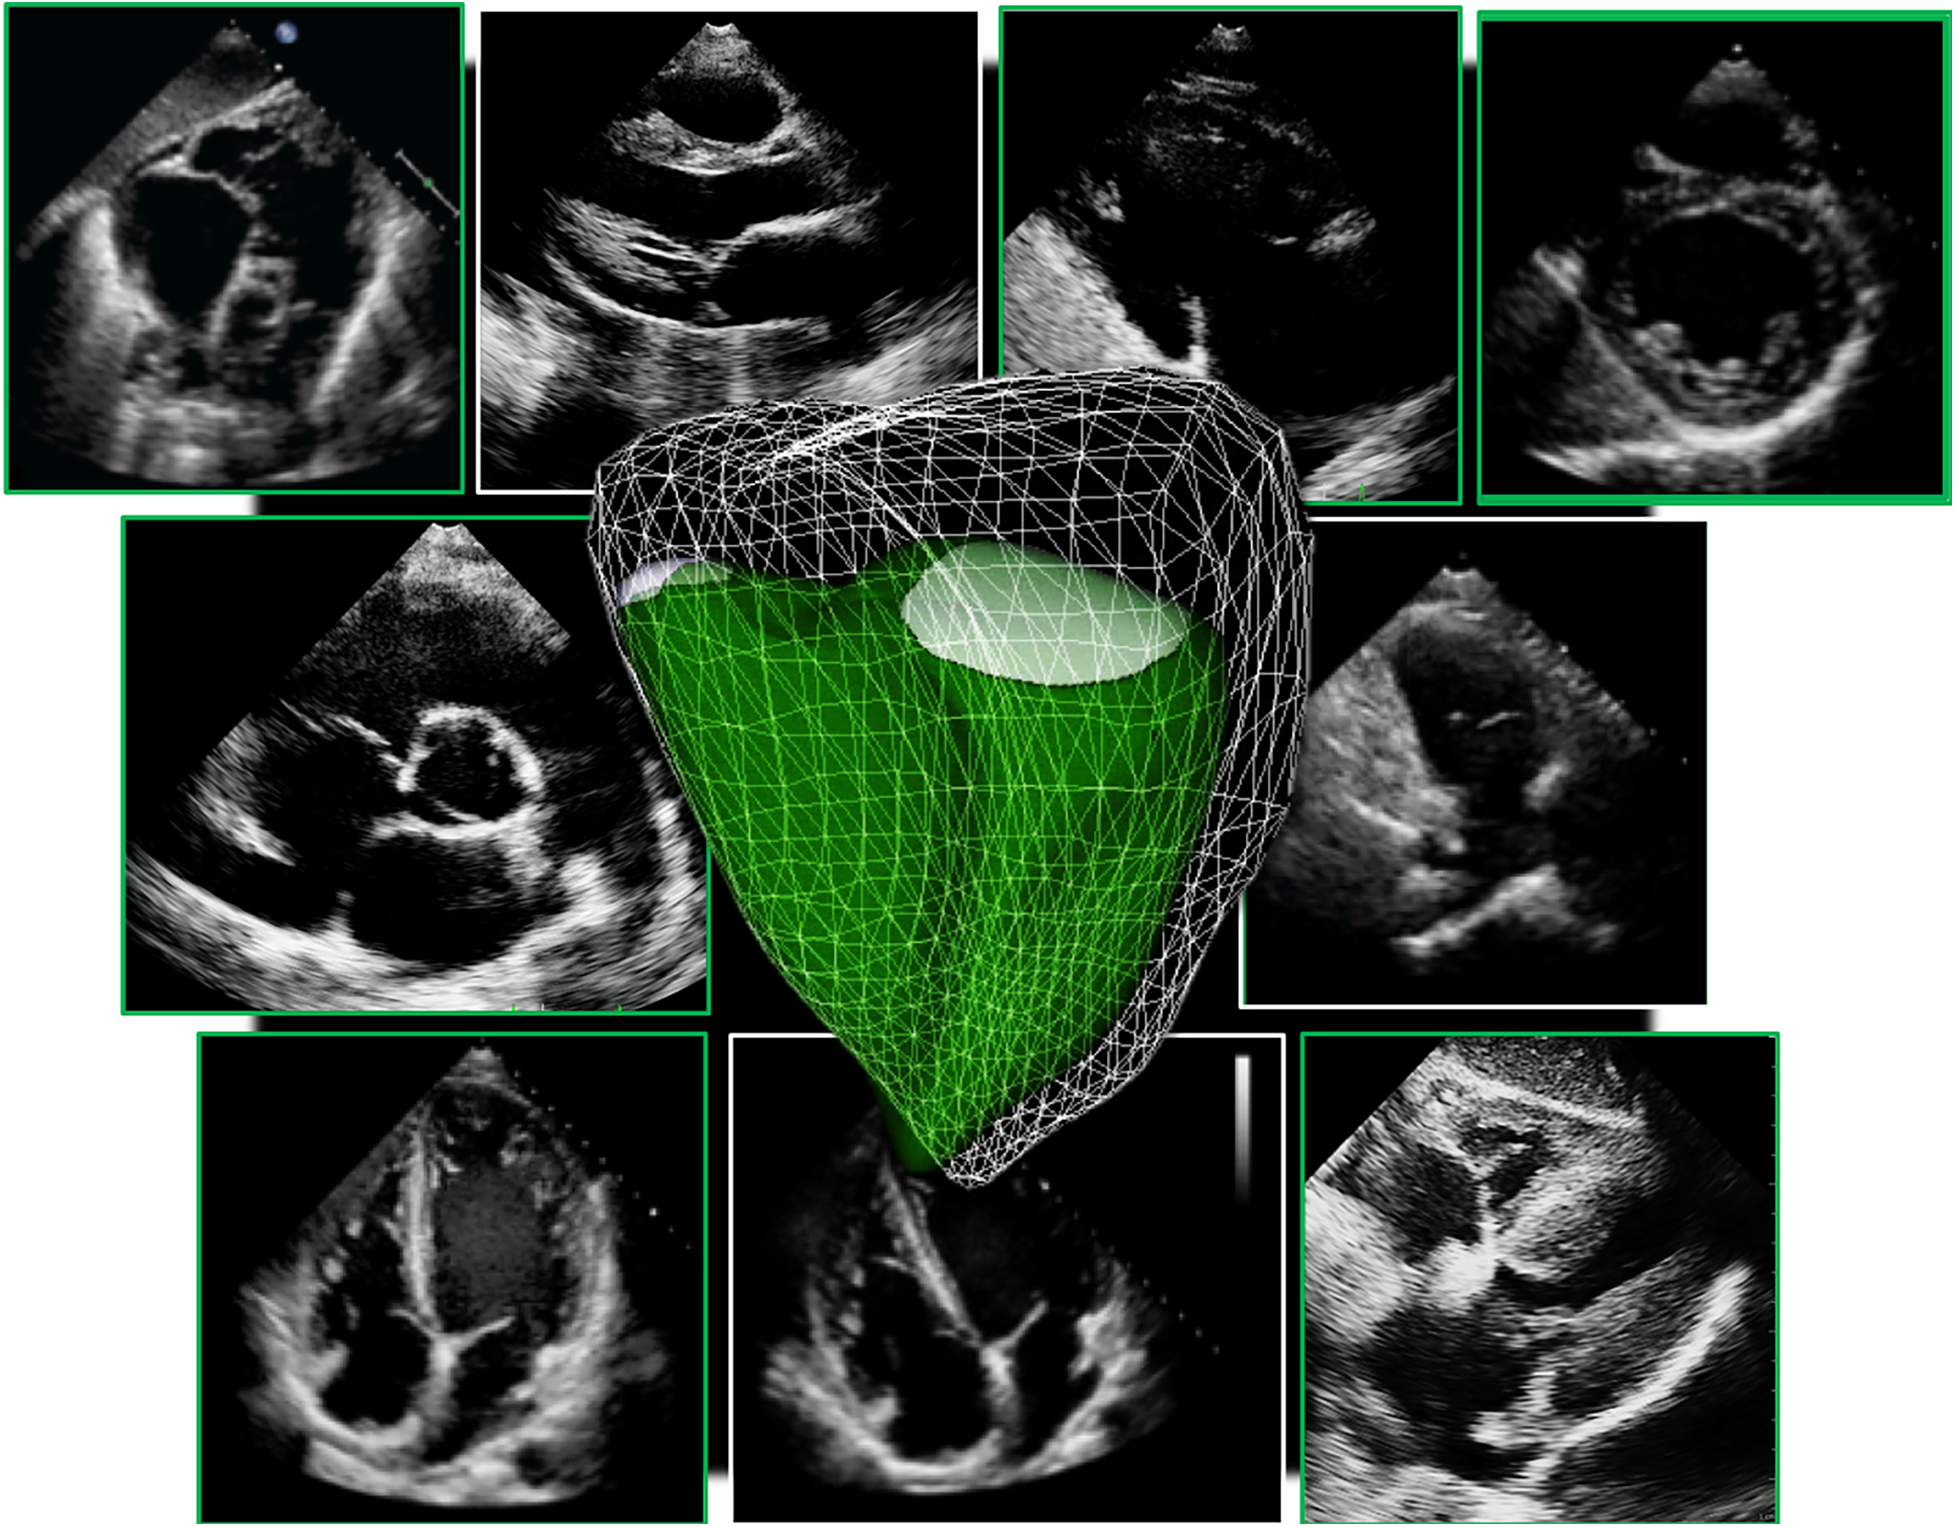

Figure 1

3d echocardiographic analysis of the right ventricle. Far left, 3D dataset of the right ventricle depicting the apical four-chamber and short-axis planes using multi-planar reconstruction. Middle panel shows endocardial tracings overlying the diastolic and systolic phases of the 2D short and long-axis cut-planes obtained from the 3D right ventricular dataset. Far right, top panel shows the 3D endocardial rendered surface while bottom panel shows the volumes obtained after automated software analysis throughout the cardiac cycle.